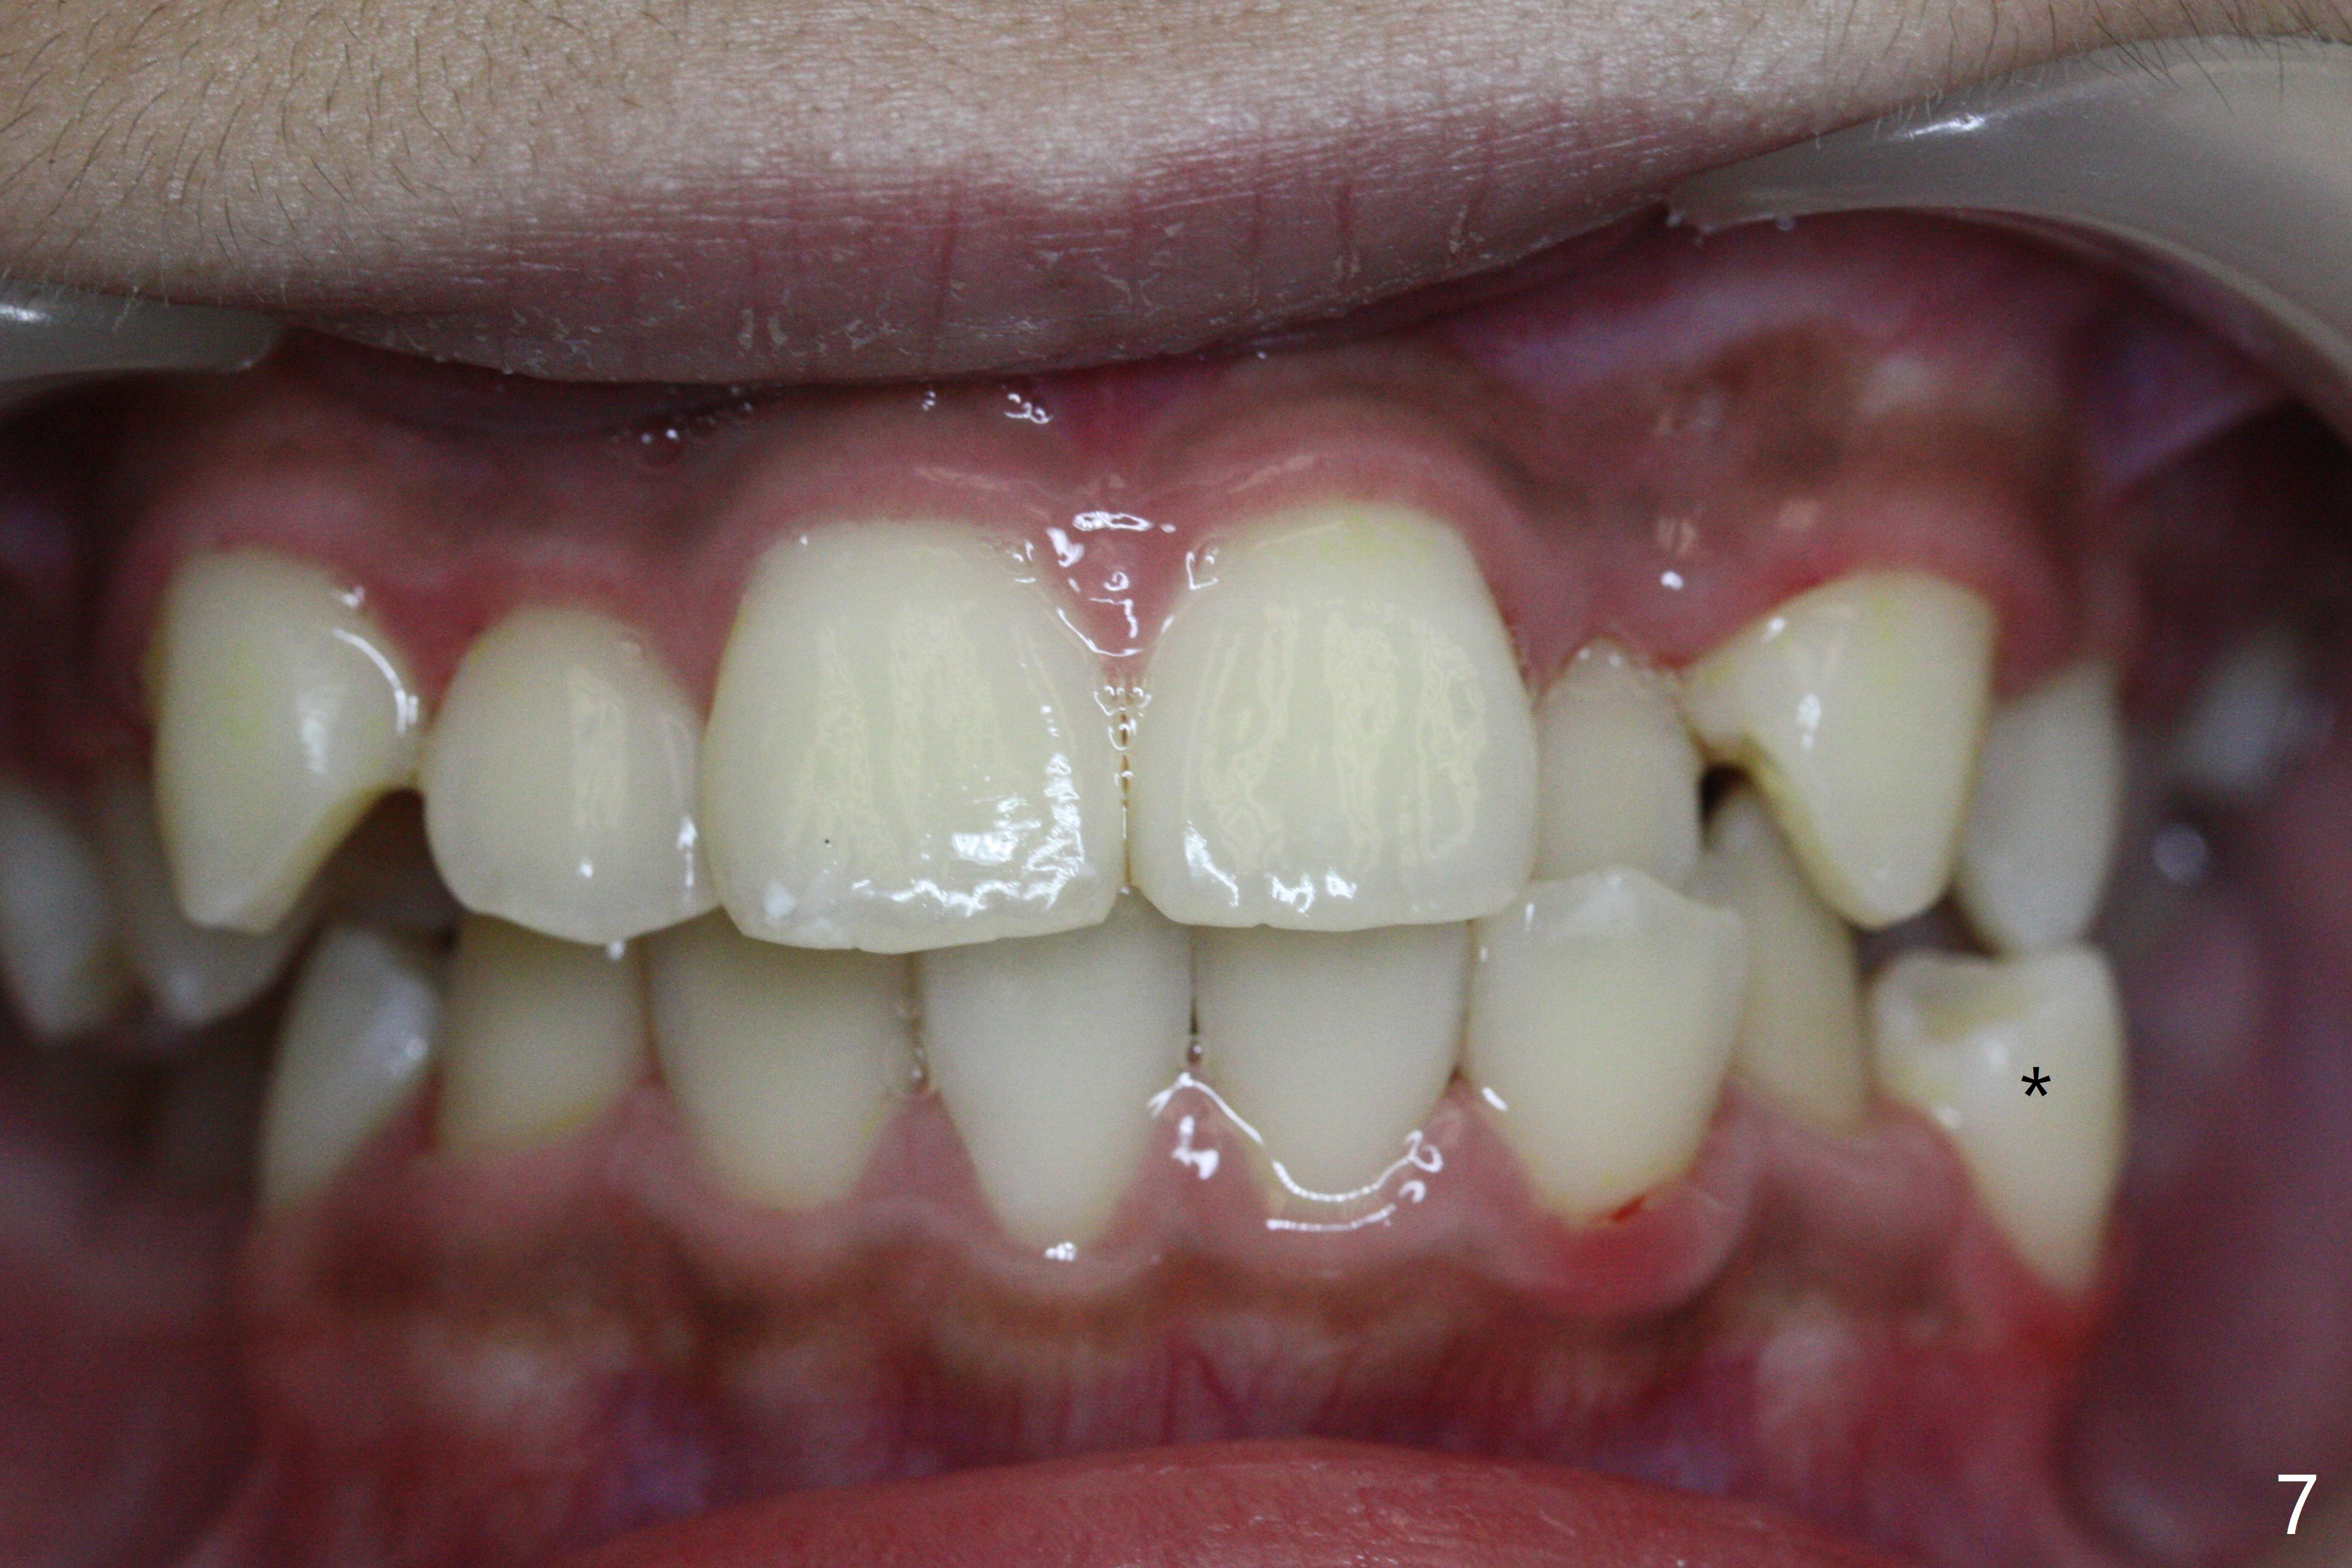

A 13-year-old man has protrusive lips (Fig.1,3,4) with upper midline deviation to the left (Fig.2).  Crowding is severe with LR5 severe lingual inclination (Fig.5,6,10).  To facilitate L6s' uprighting (Fig.10), LR5 and 3 of the 1st bicuspids will be extracted (Fig.6-8 x or *) and molar bands with lingual cleats will be used for the lower.  Cross arch molar retraction will be initiated immediately.  Open coil spring will be placed between UL1 and 3 with the 1st wires to correct the upper midline deviation and to gain the space for UL2.

The patient will return 2 months post extraction.  Shifting is expected to occur next to extraction sites (*) as indicated by arrows in Fig.9,11.  Take photos if it is the case.  Place bracket at UL2 if there is no space issue, but upside down (why?).  The most flexible wire is anticipated.  To establish Class I occlusion when wires are stiffer (18ss), LL5,6 will be mesialized as equally as LL3 distalized, while UL5,6 maintained basically in situ (Fig.11).  How to accomplish?